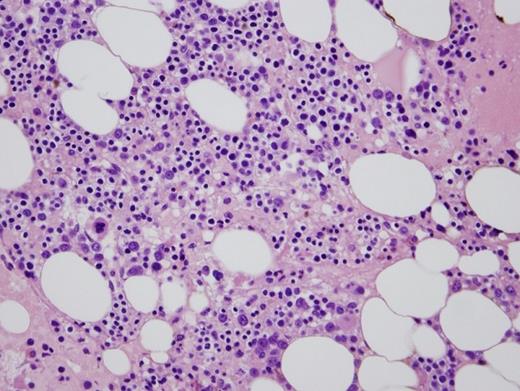

In this case, the patient presented with peripheral cytopenia only following renal transplantation while on mycophenolate mofetil and tacrolimus (MMF/TAC) for immunosuppression. Congenital PHA and autoimmune disorders (options A and E, respectively) are highly unlikely with this clinical presentation. Leukopenia and PPHA caused by infection (option B) is possible, especially in the setting of immunosuppression. However, there was no evidence of infection after clinical investigation. A bone marrow biopsy and aspiration revealed a hypocellular marrow with myeloid hypoplasia (Figure 2). MMF/TAC have been reported to cause PPHA with concurrent neutropenia and myeloid hypoplasia, with the degree of hypolobation correlated with the degree of neutropenia. This may be more severe in patients also on ganciclovir. Thus, this patient's neutropenia is likely due to an iatrogenic drug effect. The patient's anemia may be due to his renal dysfunction. Given these possible etiologies for the patient's cytopenias, there is insufficient evidence for a myelodysplastic syndrome (MDS). Furthermore, cytogenetic and molecular diagnostic (next generation sequencing-based assay) tests failed to reveal any chromosomal or molecular abnormalities commonly associated with a clonal myeloid neoplasm, thus making the diagnosis of MDS (option C) unlikely. Therefore, reactive PPHA secondary to immunosuppressive agents MMF/TAC (option D) is the most plausible explanation in this clinical scenario.

MMF/TAC-induced PPHA is a well-recognized phenomenon and often presents with cytopenia shortly after commencing immunosuppressive agents.2,3  A synergistic effect between MMF and TAC, and potentially ganciclovir, has been reported and supports a possible interaction between these drugs.3  The mechanisms of these morphologic changes have not been elucidated. However, several hypotheses, including reversible inhibition of inosine monophosphate dehydrogenase and reduction of LBR protein expression, have been proposed.2,3  The most important differential diagnosis to exclude is MDS, as it has significant clinical implications affecting prognosis and treatment. A careful clinical history including review of medications must be sought. Examination of the peripheral blood smear and bone marrow biopsy can reveal morphologic clues. For example, in contrast to MDS, drug-induced PPHA has a higher proportion of abnormal neutrophils with an absence of dysplasia in other lineages, hypo-to-normocellular marrow, no increase in blast count, and an absence of acquired clonal cytogenetic or molecular aberrations.2  In the appropriate clinical scenario of allogenic transplantation with immunosuppression, these findings should suggest a diagnosis of drug-induced PPHA which may be confirmed by restoration of normal neutrophil numbers and morphology upon discontinuation of the responsible drugs.3